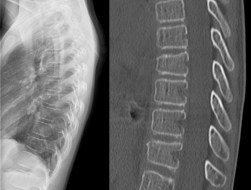

les traumatismes du rachis de l’enfant sont très différents de ceux de l’adulte en raison des propriétés mécaniques propres à l’enfant : squelette peu ossifié, très souple, volume de la tête important. en conséquence, le rachis cervical supérieur est plus souvent atteint, d’autant plus que l’enfant est petit ; chez les enfants plus grands, on retrouve souvent des fractures multi-étagées du rachis thoraco-lombaire, qui sont le plus souvent traitées par corset. il faut également chercher une fragilité particulière liée à une carence en vitamine D. par ailleurs, il existe des pathologies rachidiennes spécifiques de l’enfant, dans le cadre des traumatismes obstétricaux et des traumatismes non accidentels.

- les traumatismes du rachis thoracique et lombaire

d’une manière générale, les lésions sont d’autant plus haut sur le rachis que l’enfant est petit ; ceci reflète l’importance du poids de la tête par rapport au reste du corps. une fracture lombaire en dessous de 9 ans doit donc faire rechercher une fragilité osseuse